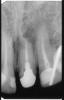

Hercule Опубликовано 25 ноября, 2012 Автор Поделиться Опубликовано 25 ноября, 2012 28 ноября :Апрель перед резекцией:Май после резекции:Июль после резекции: Скриншоты от 3Д Ссылка на комментарий